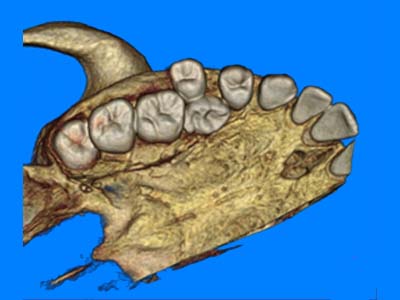

Pro Patient: Our state-of-the-art cone-beam computed tomography (CBCT) technology could selectively image the sinus, oral maxillofacial, para-nasal sinuses, ear & throat regions.

Our quick scan technology is specific for 3D imaging of the oral maxillofacial region. The actual Oral Maxillofacial CT Scan takes less than a minute. It is done in a standing or sitting position with the patient wearing their street clothes underneath a protective vest. Moreover, waiting time for the procedure & results is minimal.

Proactive Dental Management thru our 3D Imaging Manipulation Software

With Oral Maxillofacial CT Scans, your dentist enhances his ability to proactively manage your health concern thru accurate diagnosis & better treatment planning. Moreover, the patient benefits from a painless,low radiation dose CT Scan procedure.